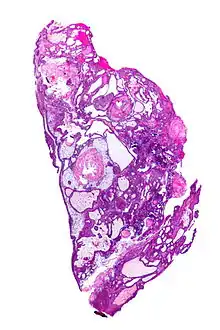

- Papillary craniopharyngiomas are characterized by BRAFv600E mutations.[24]

The papillary type rarely calcifies. A vast majority of craniopharyngiomas in children are adamantinomatous, whereas both subtypes are common in adults. Mixed-type tumors also occur.[25]

Micrograph showing a papillary craniopharyngioma, HPS stain